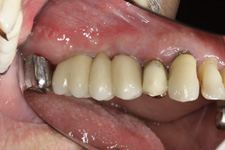

V případě chybění většího počtu zubů v postranních úsecích čelistí je možné ošetření pomocí implantátů, které nahradí ošetření pomocí snímacích náhrad kotvených na zbývajících zubech nebo patře.

Podmínkou je opět dostatečné množství kosti.

Protetické řešení může být pomocí můstku, který je kotvený na implantátech nebo pomocí jednotlivých korunek na implantátech.